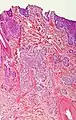

Nodular basal-cell carcinoma

.jpg.webp)

Nodular basal-cell carcinoma (also known as "classic basal-cell carcinoma") accounts for 50% of all BCC.[21] It most commonly occurs on the sun-exposed areas of the head and neck.[22]: 748 [23]: 646 Histopathology shows aggregates of basaloid cells with well-defined borders, showing a peripheral palisading of cells and one or more typical clefts.[21] Such clefts are caused by shrinkage of mucin during tissue fixation and staining.[24] Central necrosis with eosinophilic, granular features may be also present, as well as mucin. The heavy aggregates of mucin determine a cystic structure. Calcification may be also present, especially in long-standing lesions.[21] Mitotic activity is usually not so evident, but a high mitotic rate may be present in more aggressive lesions.[21] Adenoidal BCC can be classified as a variant of NBCC, characterized by basaloid cells with a reticulated configuration extending into the dermis.[21]

Cleft.